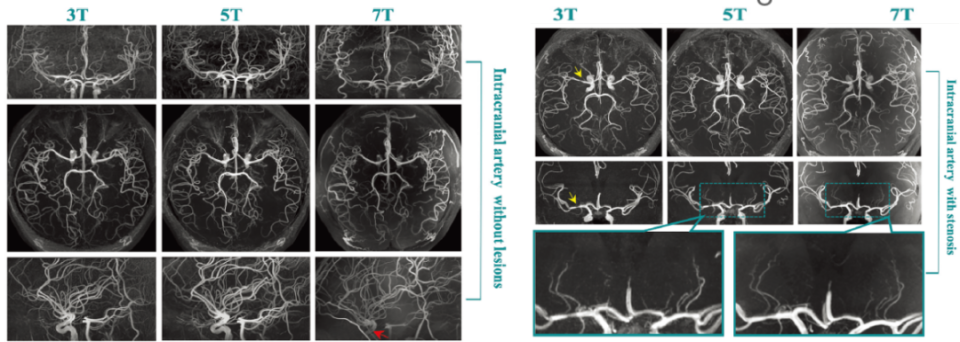

2022年,曾蒙苏教授团队与复旦大学张江国际脑影像中心合作的基于联影医疗5T磁共振最新研究成果登上国际顶级放射学期刊《Radiology》(if=29.014) ,该研究发现5T脑动脉TOF-MRA在图像质量和脑动脉远端分支及侧支小动脉的呈现上与7T效果近平相当,而显著优于常规3T成像。

代表性TOF-MRA图像。注:7-T MRI 扫描显示颈动脉虹吸管中的信号强度损失(红色箭头)。 在左侧大脑中动脉的狭窄部位(黄色箭头),5-T 图像上的豆纹动脉和 7 T 图像上的豆纹动脉均可见。